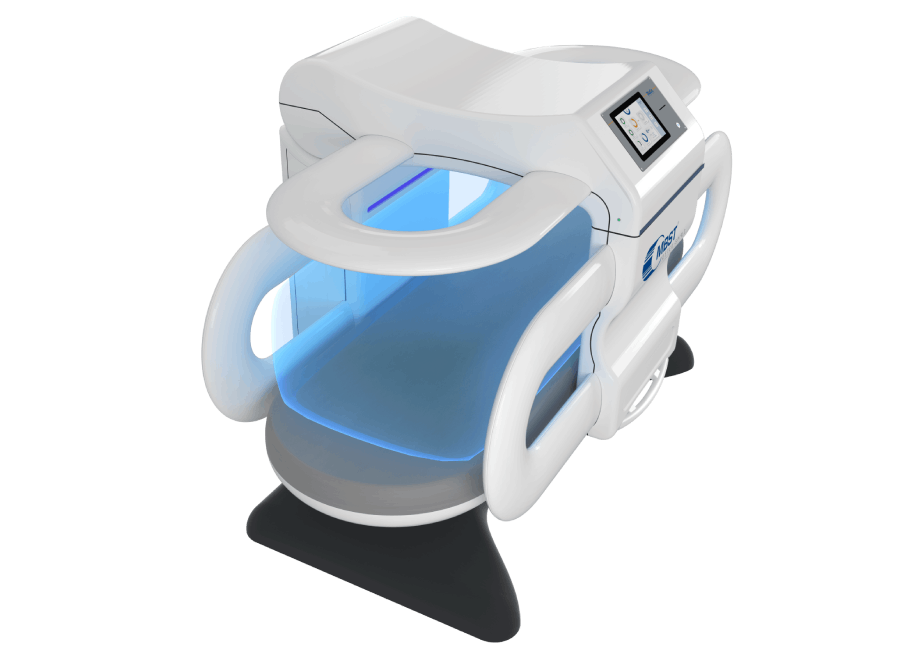

MBST®: resonancia magnética con enfoque terapéutico

MBST® es una terapia no invasiva que aplica campos electromagnéticos basados en el principio de la resonancia magnética con un fin terapéutico. En la sesión, el cuerpo recibe señales físicas controladas que buscan estimular procesos del tejido y apoyar la recuperación del sistema musculoesquelético.

3) Así es una sesión

60 minutos, silenciosa e indolora; generalmente no requiere retirar joyería o piercings.

MBST® es una terapia de uso clínico, aplicada por profesionales de la salud. Su fabricación certificada por TÜV respalda estándares de calidad, seguridad y confiabilidad a nivel internacional.